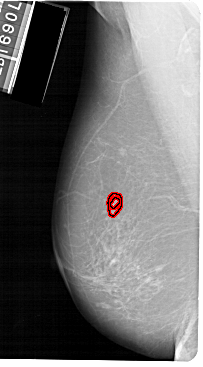

FILE: A_1149_1.LEFT_MLO.OVERLAY

TOTAL_ABNORMALITIES 1

ABNORMALITY 1

LESION_TYPE MASS SHAPE IRREGULAR MARGINS SPICULATED

ASSESSMENT 4

SUBTLETY 2

PATHOLOGY MALIGNANT

TOTAL_OUTLINES 2

BOUNDARY

CORE